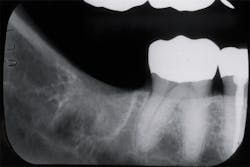

When a radiograph is taken, the dental professional may see what appears to be the outline of the root socket where an extraction has occurred, usually many years prior to any complaints (figures 1 and 2). This is a residual socket or residual root socket. The outline of the tooth’s root cavity is faintly visible, and when examined surgically, it may be hollow or filled with dense fibrous scar tissue, granulation tissue, or very immature bone.

Figure 2: Residual sockets in the same left mandible. Courtesy of Dr. Jerry E. Bouquot.